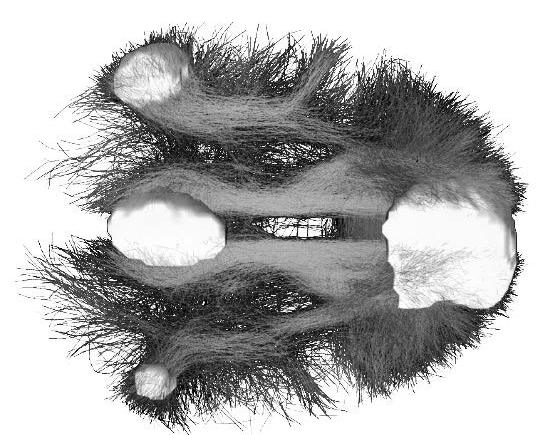

Коннектом мозга: визуализация связей и нейронных путей